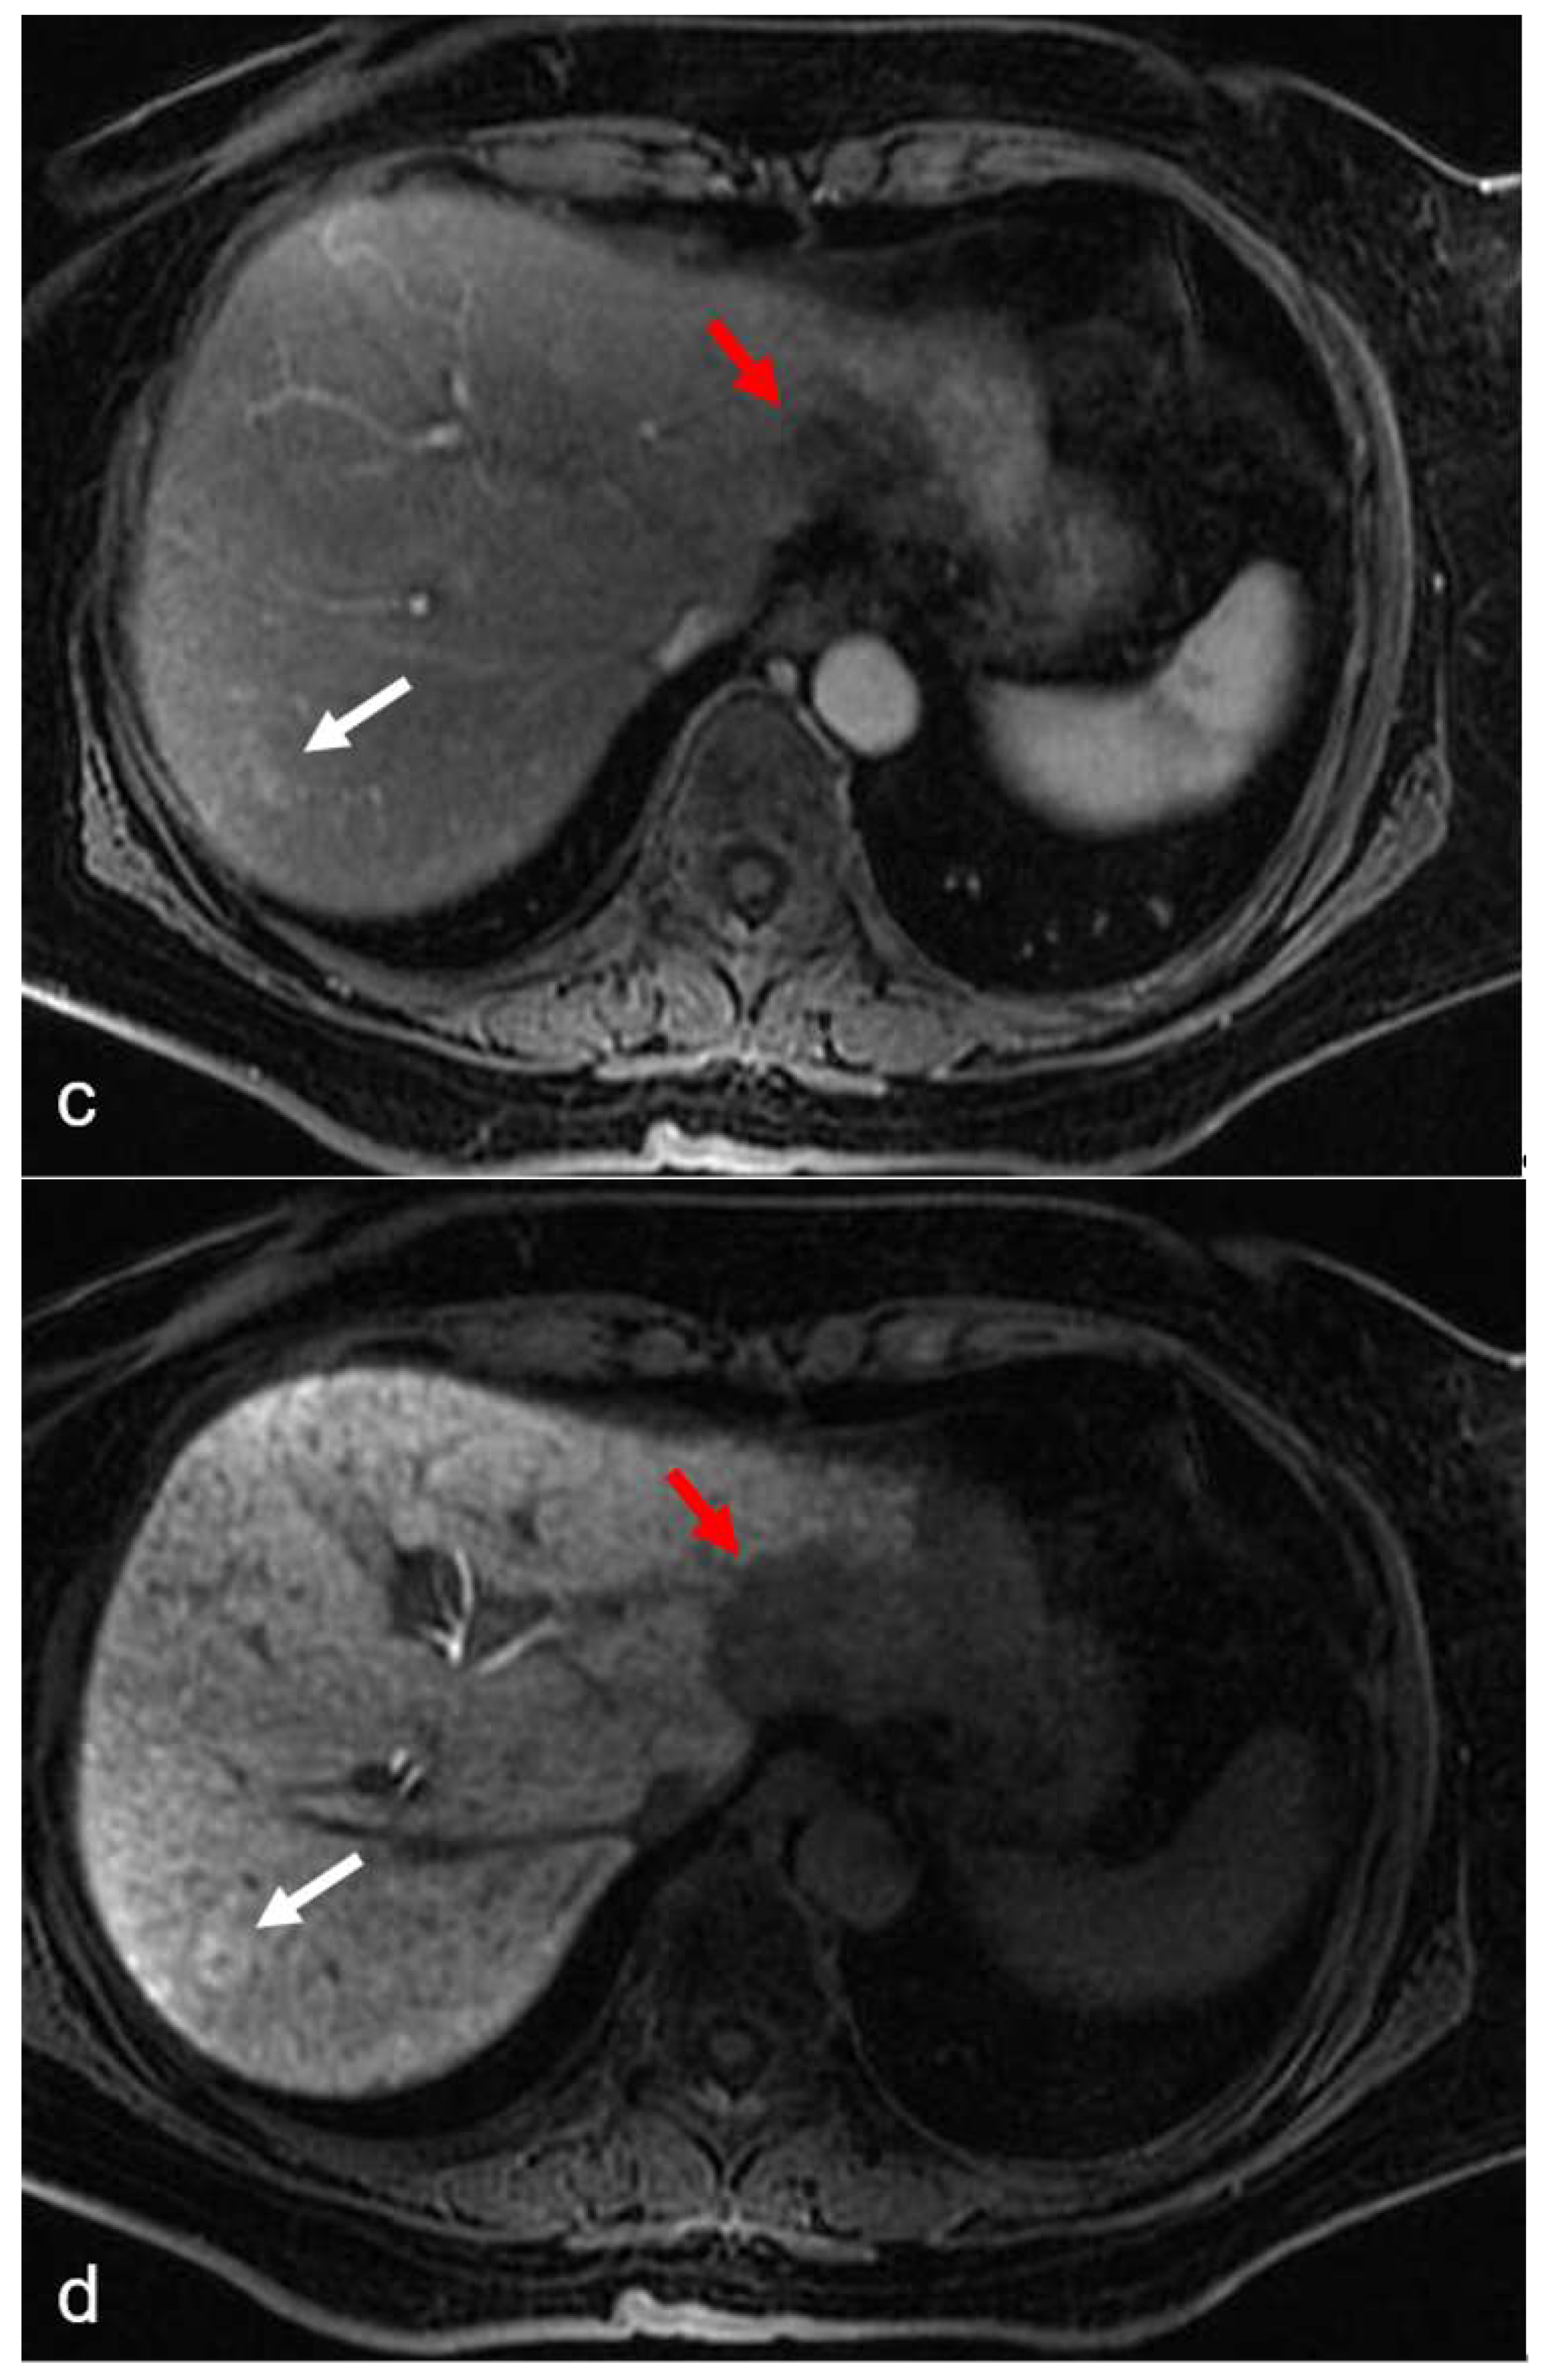

- Yoneda, N.; Matsui, O.; Ikeno, H.; Inoue, D.; Yoshida, K.; Kitao, A.; Kozaka, K.; Kobayashi, S.; Gabata, T.; Ikeda, H.; et al. Correlation between Gd-EOB-DTPA-enhanced MR imaging findings and OATP1B3 expression in chemotherapy-associated sinusoidal obstruction syndrome. Abdom. Imaging 2015, 40, 3099–3103. [Google Scholar] [CrossRef] [PubMed]

- Shin, N.Y.; Kim, M.J.; Lim, J.S.; Park, M.S.; Chung, Y.E.; Choi, J.Y.; Kim, K.W.; Park, Y.N. Accuracy of gadoxetic acid-enhanced magnetic resonance imaging for the diagnosis of sinusoidal obstruction syndrome in patients with chemotherapy-treated colorectal liver metastases. Eur. Radiol. 2012, 22, 864–871. [Google Scholar] [CrossRef]